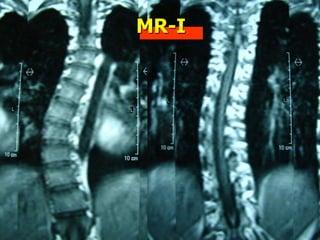

Προεγχειρητική

εκτίμηση και

σχεδιασμός

Stable vertebra

Δυναμικές x-rays

CT Scan

MR-I

Neuro-monitoring

Navigation system